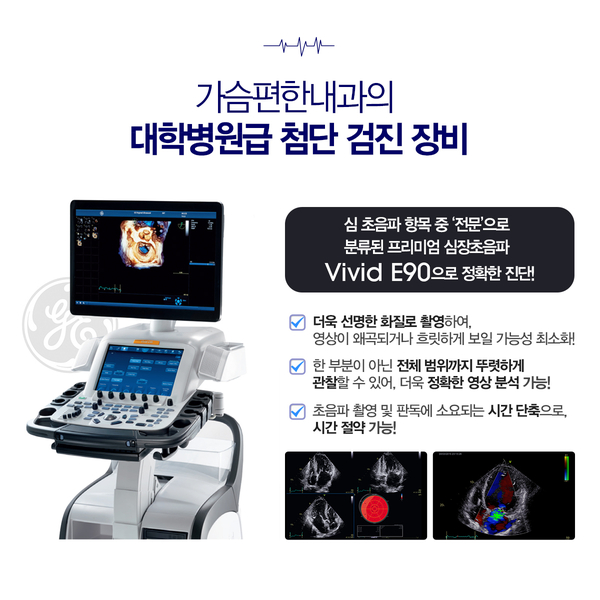

- 심장초음파 검사: 심장 구조와 기능을 실시간으로 확인하여 심장 근육 이상이나 판막 질환 등을 진단할 수 있습니다.

가슴편한내과는 삼성서울병원과 미국 메이오클리닉에서 진료 경험을 쌓은 대학병원 출신의 순환기내과 전문의 2인이 직접 진단과 검사를 시행하며, 검사 결과를 환자분께 직접 상세히 설명해 드립니다.

또한 최신형 심장초음파 장비와 운동부하 검사 장비 등 대학병원급의 첨단 의료 장비를 갖추고 있어 신뢰할 수 있는 검사 결과를 제공해 드립니다.